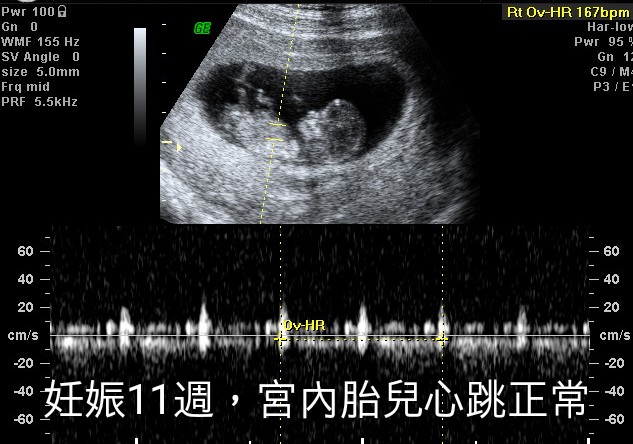

11周时候胎儿正常。

孕11周的时候,小兰到宝山医院产科门诊复查,医生发现胎儿在宫内心跳正常,小兰的左侧附件囊肿增大到了5厘米。毕竟小兰已经怀孕了,而且没有什么不舒服,因此,医生暂时没有处理小兰的左侧附件囊肿。